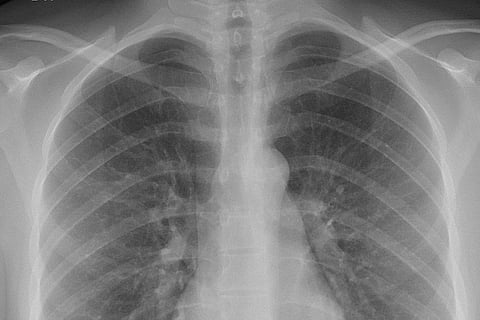

एक्स-रे के जन्म की वर्षगांठ के अवसर पर हर साल आठ नवंबर को विश्व रेडियोग्राफी दिवस मनाया जाता है। आज ऐसी दुनिया की कल्पना करना कठिन है जहां एक्स-रे मौजूद न हो। वे कई चिकित्सा निदान उपकरणों की नींव हैं और डॉक्टरों को कई प्रकार की समस्याओं का पता लगाने में मदद करते हैं।

आश्चर्य की बात यह है कि, वे इसे कुछ ही मिनटों में, पूरी तरह से दर्द रहित तरीके से करते हैं। यह कड़ी मेहनत करने वाले रेडियोग्राफरों और रेडियोलॉजिस्टों का भी जश्न मनाने का दिन है, जो एक्स-रे को संभव बनाते हैं।